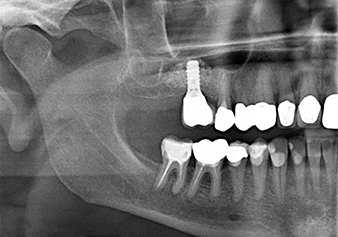

A 49-year-old female patient, a non-smoker and with nothing remarkable in her general medical history, was referred to our oral surgery practice for surgical extraction of tooth 16 and subsequent implantation. After the extraction, the patient experienced mild sinusitis trouble with the resultthat we initially waited six months before carrying out the measure. The residual bone height at the planned implant position measured 3-4 mm (Fig. 1 and 2).

Fig.1: Preoperative findings: The alveolar ridge has healed well, including sufficiently broad, keratinised gingiva.